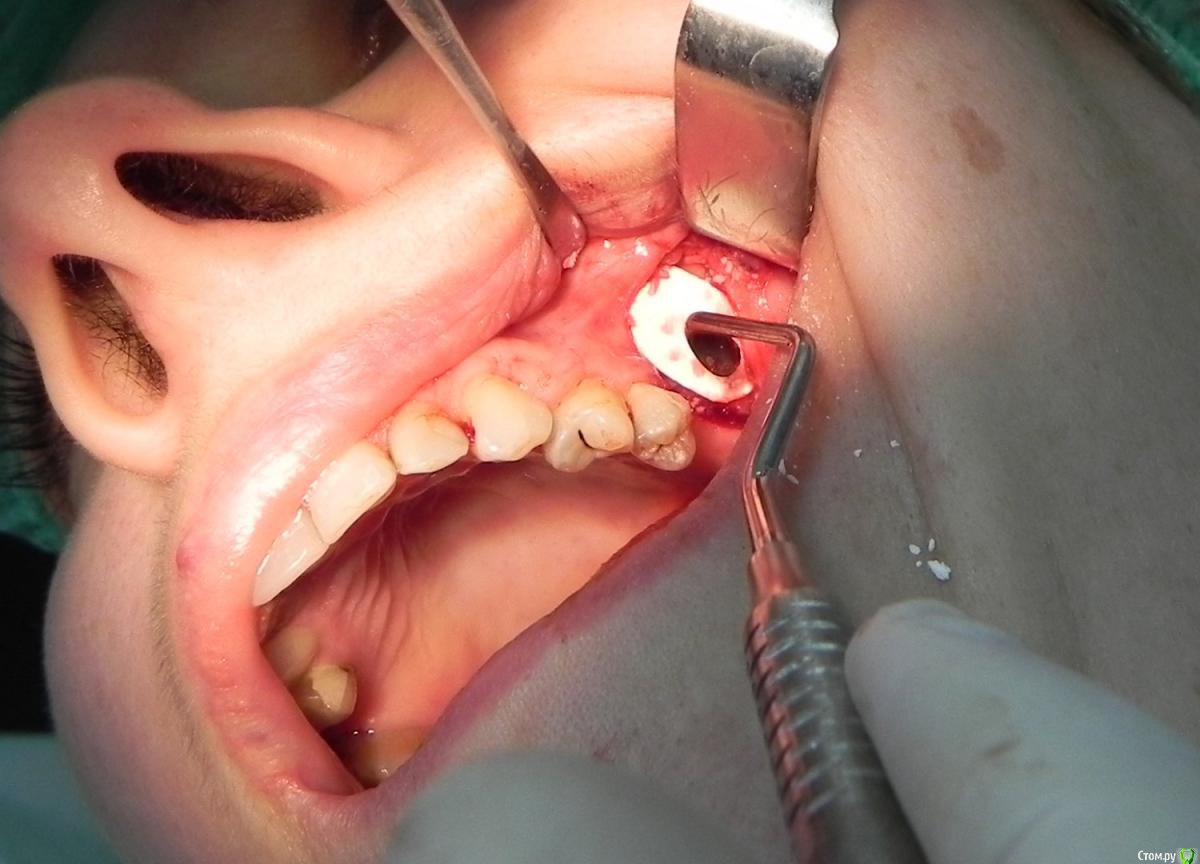

Kostoprav Опубликовано 7 августа, 2015 Поделиться Опубликовано 7 августа, 2015 доступпрепаровка шаровидной костной фрезойпри отслаивании мембраны образовалась маленькая перфа перфорацию" проклеил" коллагеновой мембранойпод мембрану внесен материалмембрана на окноготово может кому из начинающих этот пост полезен будет 1 Ссылка на комментарий

Jurai Опубликовано 7 августа, 2015 Поделиться Опубликовано 7 августа, 2015 что это между швами? дренаж? а зачем? 5 Ссылка на комментарий

Kostoprav Опубликовано 7 августа, 2015 Автор Поделиться Опубликовано 7 августа, 2015 что это между швами? дренаж? а зачем?там вообще то не один а два, второй за зубом спрятался) профилактика гематомы, я их на следующий день или два убираю Ссылка на комментарий

Популярный пост carloss Опубликовано 7 августа, 2015 Популярный пост Поделиться Опубликовано 7 августа, 2015 то есть возможность инфицирования графта через щель для дренажа исключается? 20 Ссылка на комментарий

Kostoprav Опубликовано 8 августа, 2015 Автор Поделиться Опубликовано 8 августа, 2015 то есть возможность инфицирования графта через щель для дренажа исключается?не думаю что инфекция проникнет через щель от дренажа учитывая то что дренаж удаляется через сутки и пациент принимает антибиотики, во всяком случае у меня такого не было тьфу-тьфу Ссылка на комментарий